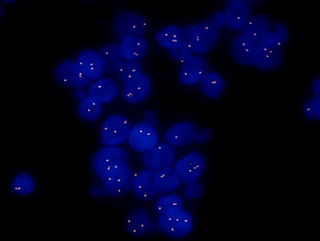

MF43-N+MSX11拍攝的FISH圖片

FISH樣品在紫外激發(fā)光的照射在,顯現(xiàn)出藍(lán)色的細(xì)胞輪廓的信號(hào),在藍(lán)色激發(fā)光的照射下在細(xì)胞內(nèi)顯現(xiàn)出綠色的探針信號(hào),在綠色激發(fā)光的照射下在細(xì)胞內(nèi)顯現(xiàn)出紅色的探針信號(hào)。

選擇細(xì)胞核邊界完整、無(wú)重疊,標(biāo)記的紅色信號(hào)和標(biāo)記的綠色信號(hào)清晰的細(xì)胞,隨機(jī)計(jì)數(shù)至少20個(gè)細(xì)胞核中雙色信號(hào)。判斷信號(hào)點(diǎn)有無(wú)分離或者有無(wú)擴(kuò)增等,并在專業(yè)的病理醫(yī)師或技術(shù)人員的指導(dǎo)下對(duì)結(jié)果進(jìn)行判讀,保證結(jié)果的準(zhǔn)確性。明美研究級(jí)正置熒光顯微鏡MF43-N采用優(yōu)良的無(wú)限遠(yuǎn)光學(xué)系統(tǒng),搭配四通道光源MG-120,熒光激發(fā)信號(hào)強(qiáng),并且可以即開(kāi)即用,可以選配單通或雙通熒光激發(fā)塊,可供選擇的熒光波段繁多且亮度高,可滿足FISH領(lǐng)域的研究需要,也應(yīng)用于生物制藥,醫(yī)學(xué)檢測(cè)、疾病預(yù)防等領(lǐng)域內(nèi)的熒光檢測(cè)。